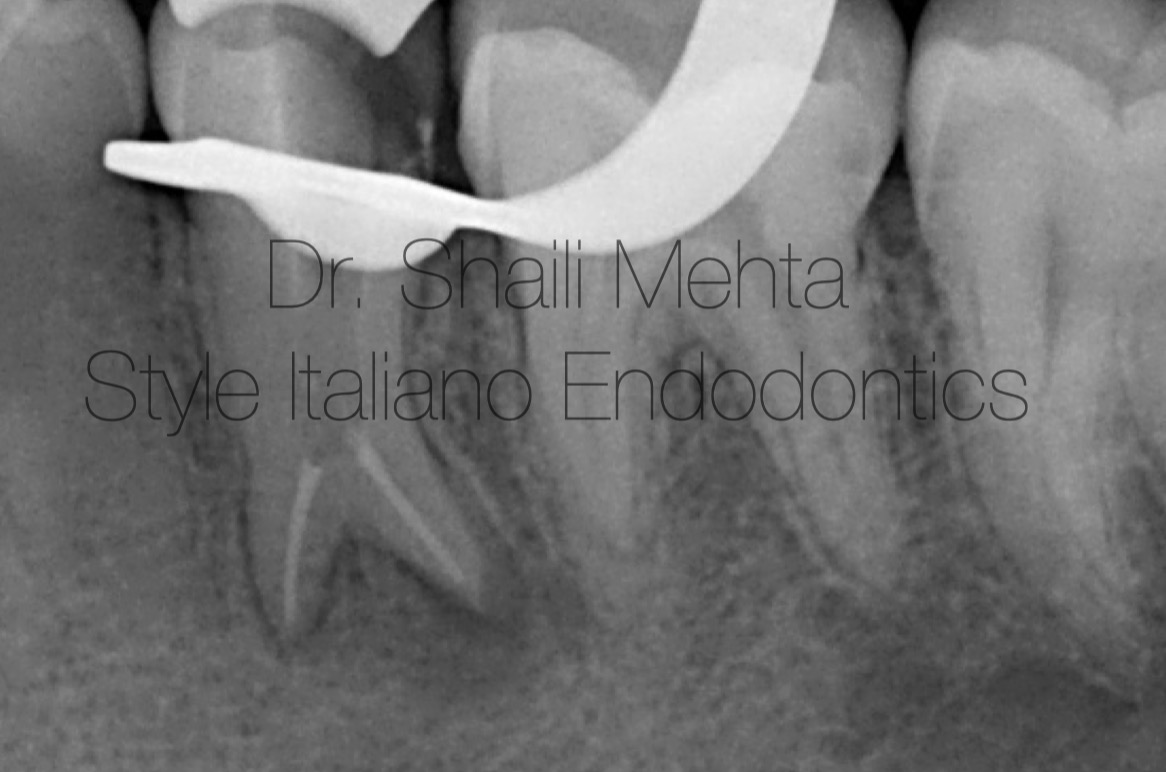

Fig. 4

Obturation was performed using gutta-percha and a modern bioceramic sealer via the warm vertical compaction technique, ensuring three-dimensional sealing of the two separate root canal systems. A post-endodontic core restoration was immediately placed, and the patient was referred for a definitive full-coverage ceramic crown to ensure a durable coronal seal.